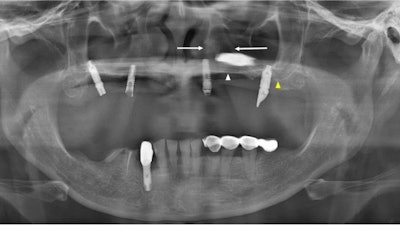

The panoramic x-ray of a 51-year-old woman. The white arrow indicates the left hard palate line, while the yellow arrow indicates the antral floor. The implant fixture is displaced into the superior cavity, but the bone between the white arrows appears to have sufficient volume. All images courtesy of Kim et al. Licensed by CC BY 4.0.

The patient was referred to the hospital after an implant migrated to her superior cavity. An x-ray revealed that one implant that was intended for the premolar region had been displaced horizontally between the boundaries of the nasal cavity and maxillary sinus, appearing to have perforated the medial wall of the maxillary sinus. A CT image confirmed that the implant had migrated to the nasal cavity.